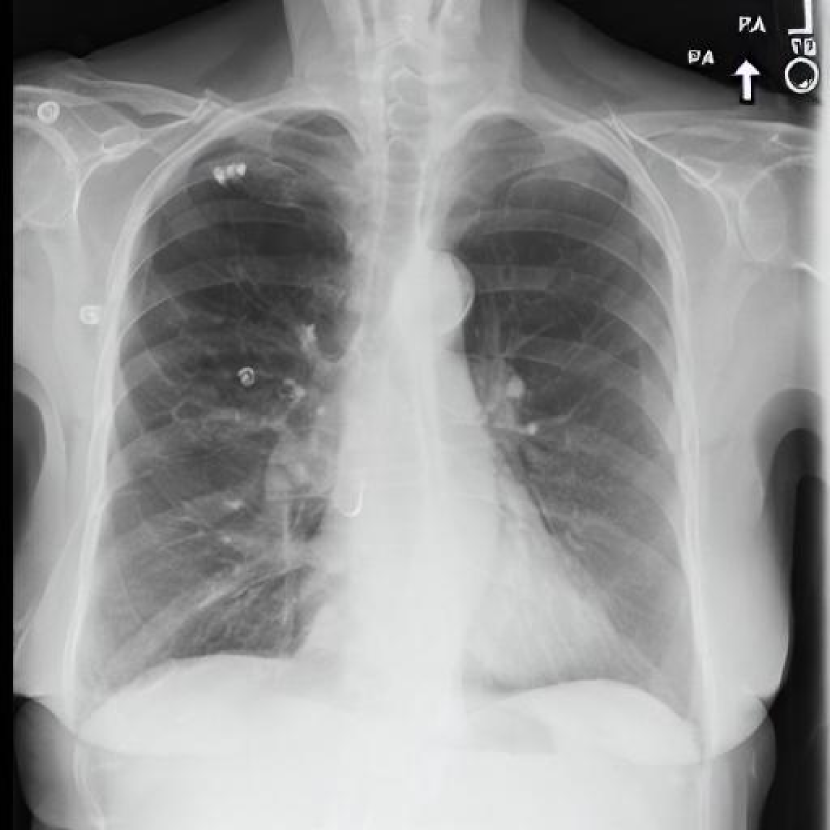

Leveraging Synthetic Data. With the advent of generative modelling tools, we are armed with the power to mitigate the problem of having a long-tail by supplementing the rare labels. We run a small experiment to evaluate whether we can use RoentGen [2], a prompt-based Stable Diffusion model to generate realistic chest X-rays and augment the training data. We generate about 5000 X-rays for training containing at least one pathology from the tail classes. We curate prompts for RoentGen by translating the Spanish reports available in the PadChest dataset to English, and also generate radiologist report-like prompts using ChatGPT 111chat.openai.com by providing curated templates. Figure 3 shows examples of prompts and the corresponding synthetic X-rays generated by RoentGen and verified by a radiologist.

Contribution of Synthetic Data. Figure 2 shows the increase in performance of the model over Table 1. This model was jointly finetuned on MIMIC CXR and a small synthetic dataset (refer Figure 3 for samples). Although the size of the synthetic dataset was too small for it to demonstrate an appreciable performance delta, these results show the promise of leveraging synthetic data to overcome the challenge of training on rare classes at least to some extent, especially since the biggest change is seen in the performance of the tail classes.